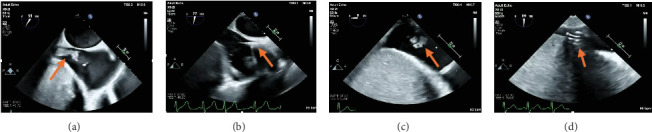

AngioVac机械抽吸系统已在文献中出现,作为一种可行的治疗选择,用于心脏手术高风险的心内肿块和血栓患者。值得注意的是,它已被证明是一种有效的治疗方式,为减少血栓在恶性肿瘤的设置。我们报告一例在晚期恶性肿瘤合并粪肠球菌心内膜炎的情况下,右心房大血栓从肝静脉延伸的重复血管血管消肿。

The AngioVac mechanical aspiration system has emerged in the literature as a viable treatment option for patients with intracardiac masses and thrombi and who are deemed high risk for cardiac surgery. Notably, it has been shown to be an effective treatment modality for the debulking of thrombi in the setting of malignancy. We present a case of repeat AngioVac debulking of a large right atrial thrombus with extension from the hepatic vein in the setting of advanced malignancy complicated by Enterococcus faecium endocarditis.